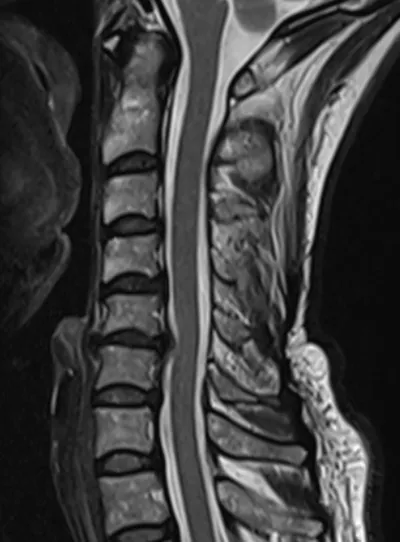

Disc osteophyte protrustion C5-C6

MRISagittalCervical Spine+1

2/6/2026